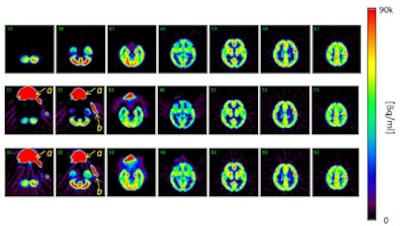

Top row: PET images from the head phantom. Middle row: PET images from the head phantom plus facemask, including out-of-FOV scatter correction. Bottom row: PET images from the phantom plus facemask, but with the out-of-FOV scatter compensation disabled. Arrows indicate the radioactivity in the face mask (a) and O-15 supply tube (b).

Using the core SSS scatter correction, when the facemask was included in the scan inside the scanner's FOV, counts in the head phantom deviated from the reference scan by less than ± 2%. When the lung phantom was placed on the scanner couch, the error increased slightly to 3%. Positioning the facemask partially outside the FOV, where the SSS technique could not correct for scatter increased errors to 2% to 6%.

When the out-of-FOV scatter correction was included, however, errors increased significantly, with the scanner underestimating counts from the brain phantom in all experiments. For example, when the facemask was partially outside the FOV, counts were underestimated by 2% to 19%.